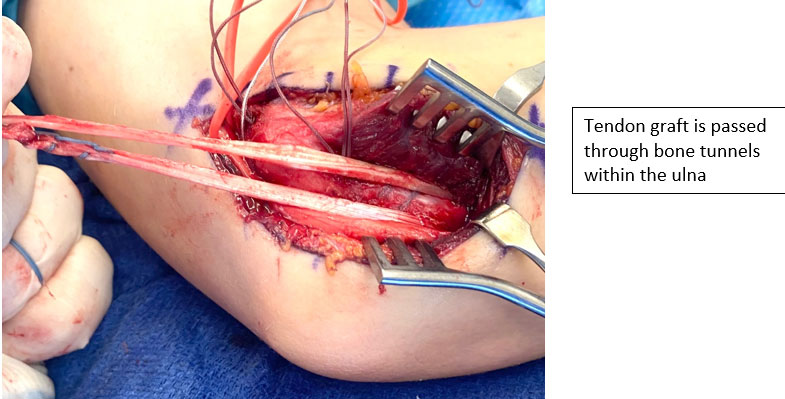

- In general, surgical techniques requires recreation of ulnar and humeral tunnels for placement of a tendon graft to reconstruct the ulnar collateral ligament

Palmaris Longus is a tendon that is commonly harvested from the forearm for graft usage. When a palmaris is not present (15-20%) a hamstring tendon can be utilized